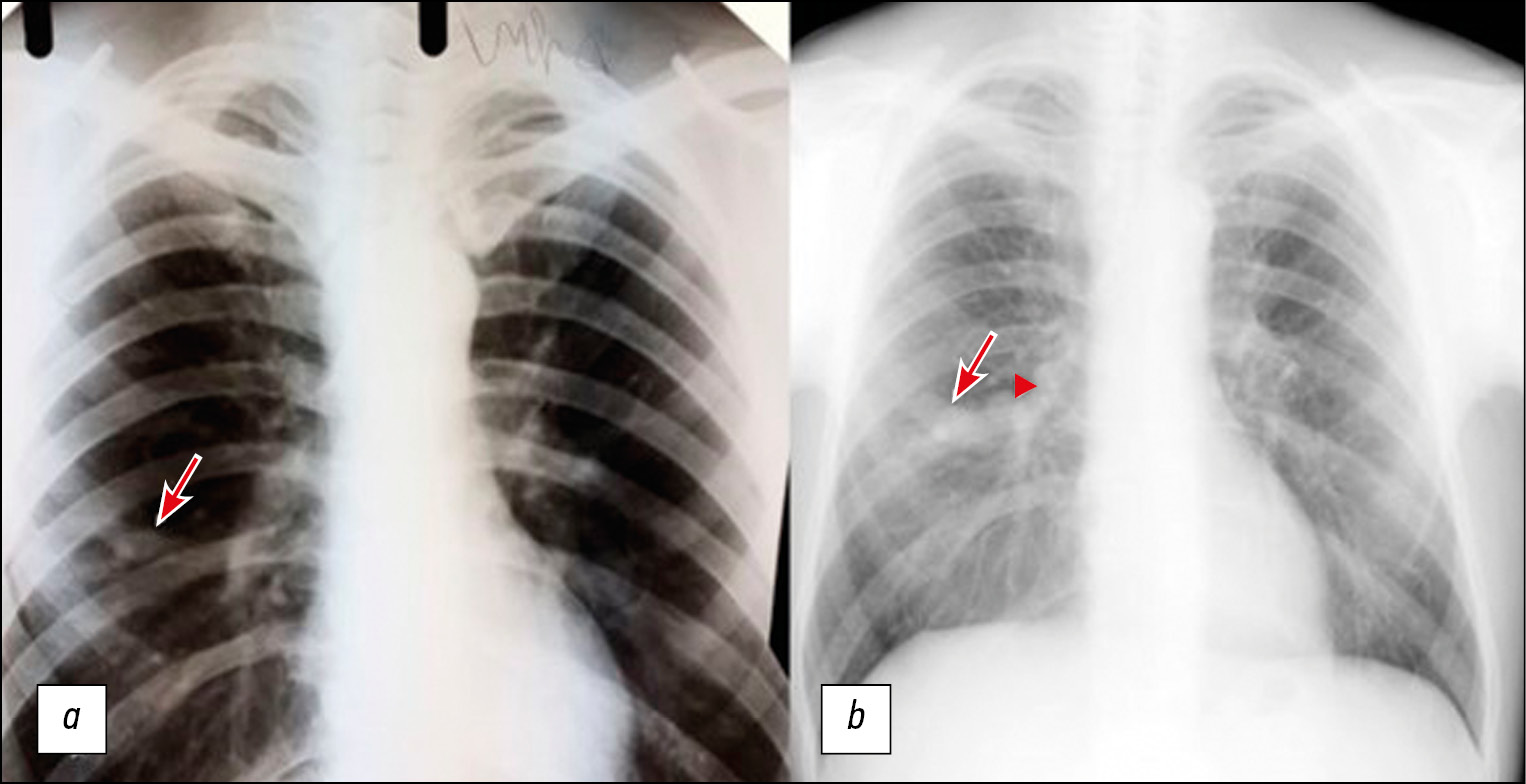

Fig. 1. Patient, 56 years old, chest x-ray: a - at the initial examination at the age of 41 in the middle section of the right lung, a seal area of a branched tubular structure is determined (arrow); b - 15 years later, there was an increase in the size of the bronchocele (arrow) and the appearance of a rounded formation in the medial regions bronchocele (arrowhead).

The history assessment revealed that he was examined for pneumonia 15 years ago. Despite the positive dynamics based on clinical studies, during the course of antibiotic therapy, radiological findings did not correspond to the typical course of regression of infiltrative lungs changes in pneumonia. X-ray imaging of the chest revealed an area of induration of a tubular branched structure in the middle section of the right lung (Fig. 1, a). Additional studies, including computed tomography of the chest with intravenous contrast enhancement, fibrobronchoscopy, and immunological and bacteriological studies, did not detect tuberculosis or an oncological process. Computed tomography data were presented as selective scans on a film carrier, which revealed a local, single branched structure with smooth, clear contours, located along the subsegmental bronchi of the middle lobe of the right lung (finger in glove sign), with homogeneous contents (Fig. 2), so the patient was diagnosed with bronchogenic retention cyst (bronchocele) on the middle lobe of the right lung. Subsequently, follow-up studies were performed annually by X-ray examination of the chest, and stable changes were observed.

Prior to the present admission, the patient underwent a medical examination at his workplace with harmful working conditions. X-ray imaging of the chest revealed an increase in the size of the previously determined bronchocele (Fig. 1, b), as well as a new round lesion in the medial sections of the bronchocele with calcifications along the lesion contour (Fig. 1, b). To clarify the nature of the changes, the patient underwent contrast-enhanced computed tomography of the chest, which detected a single branched V-shaped structure with a clear contour in the middle lobe of the right lung, and homogeneous contents located along the subsegmental bronchi (finger in glove sign) were preserved. At the base of the bronchocele, a rounded lesion with a smooth, clear contour is noted, almost completely overlapping the bronchus B4 lumen, and single calcifications were found along the periphery with signs of contrast accumulation in the venous phase from +29 HU to +112 HU (Fig. 3).